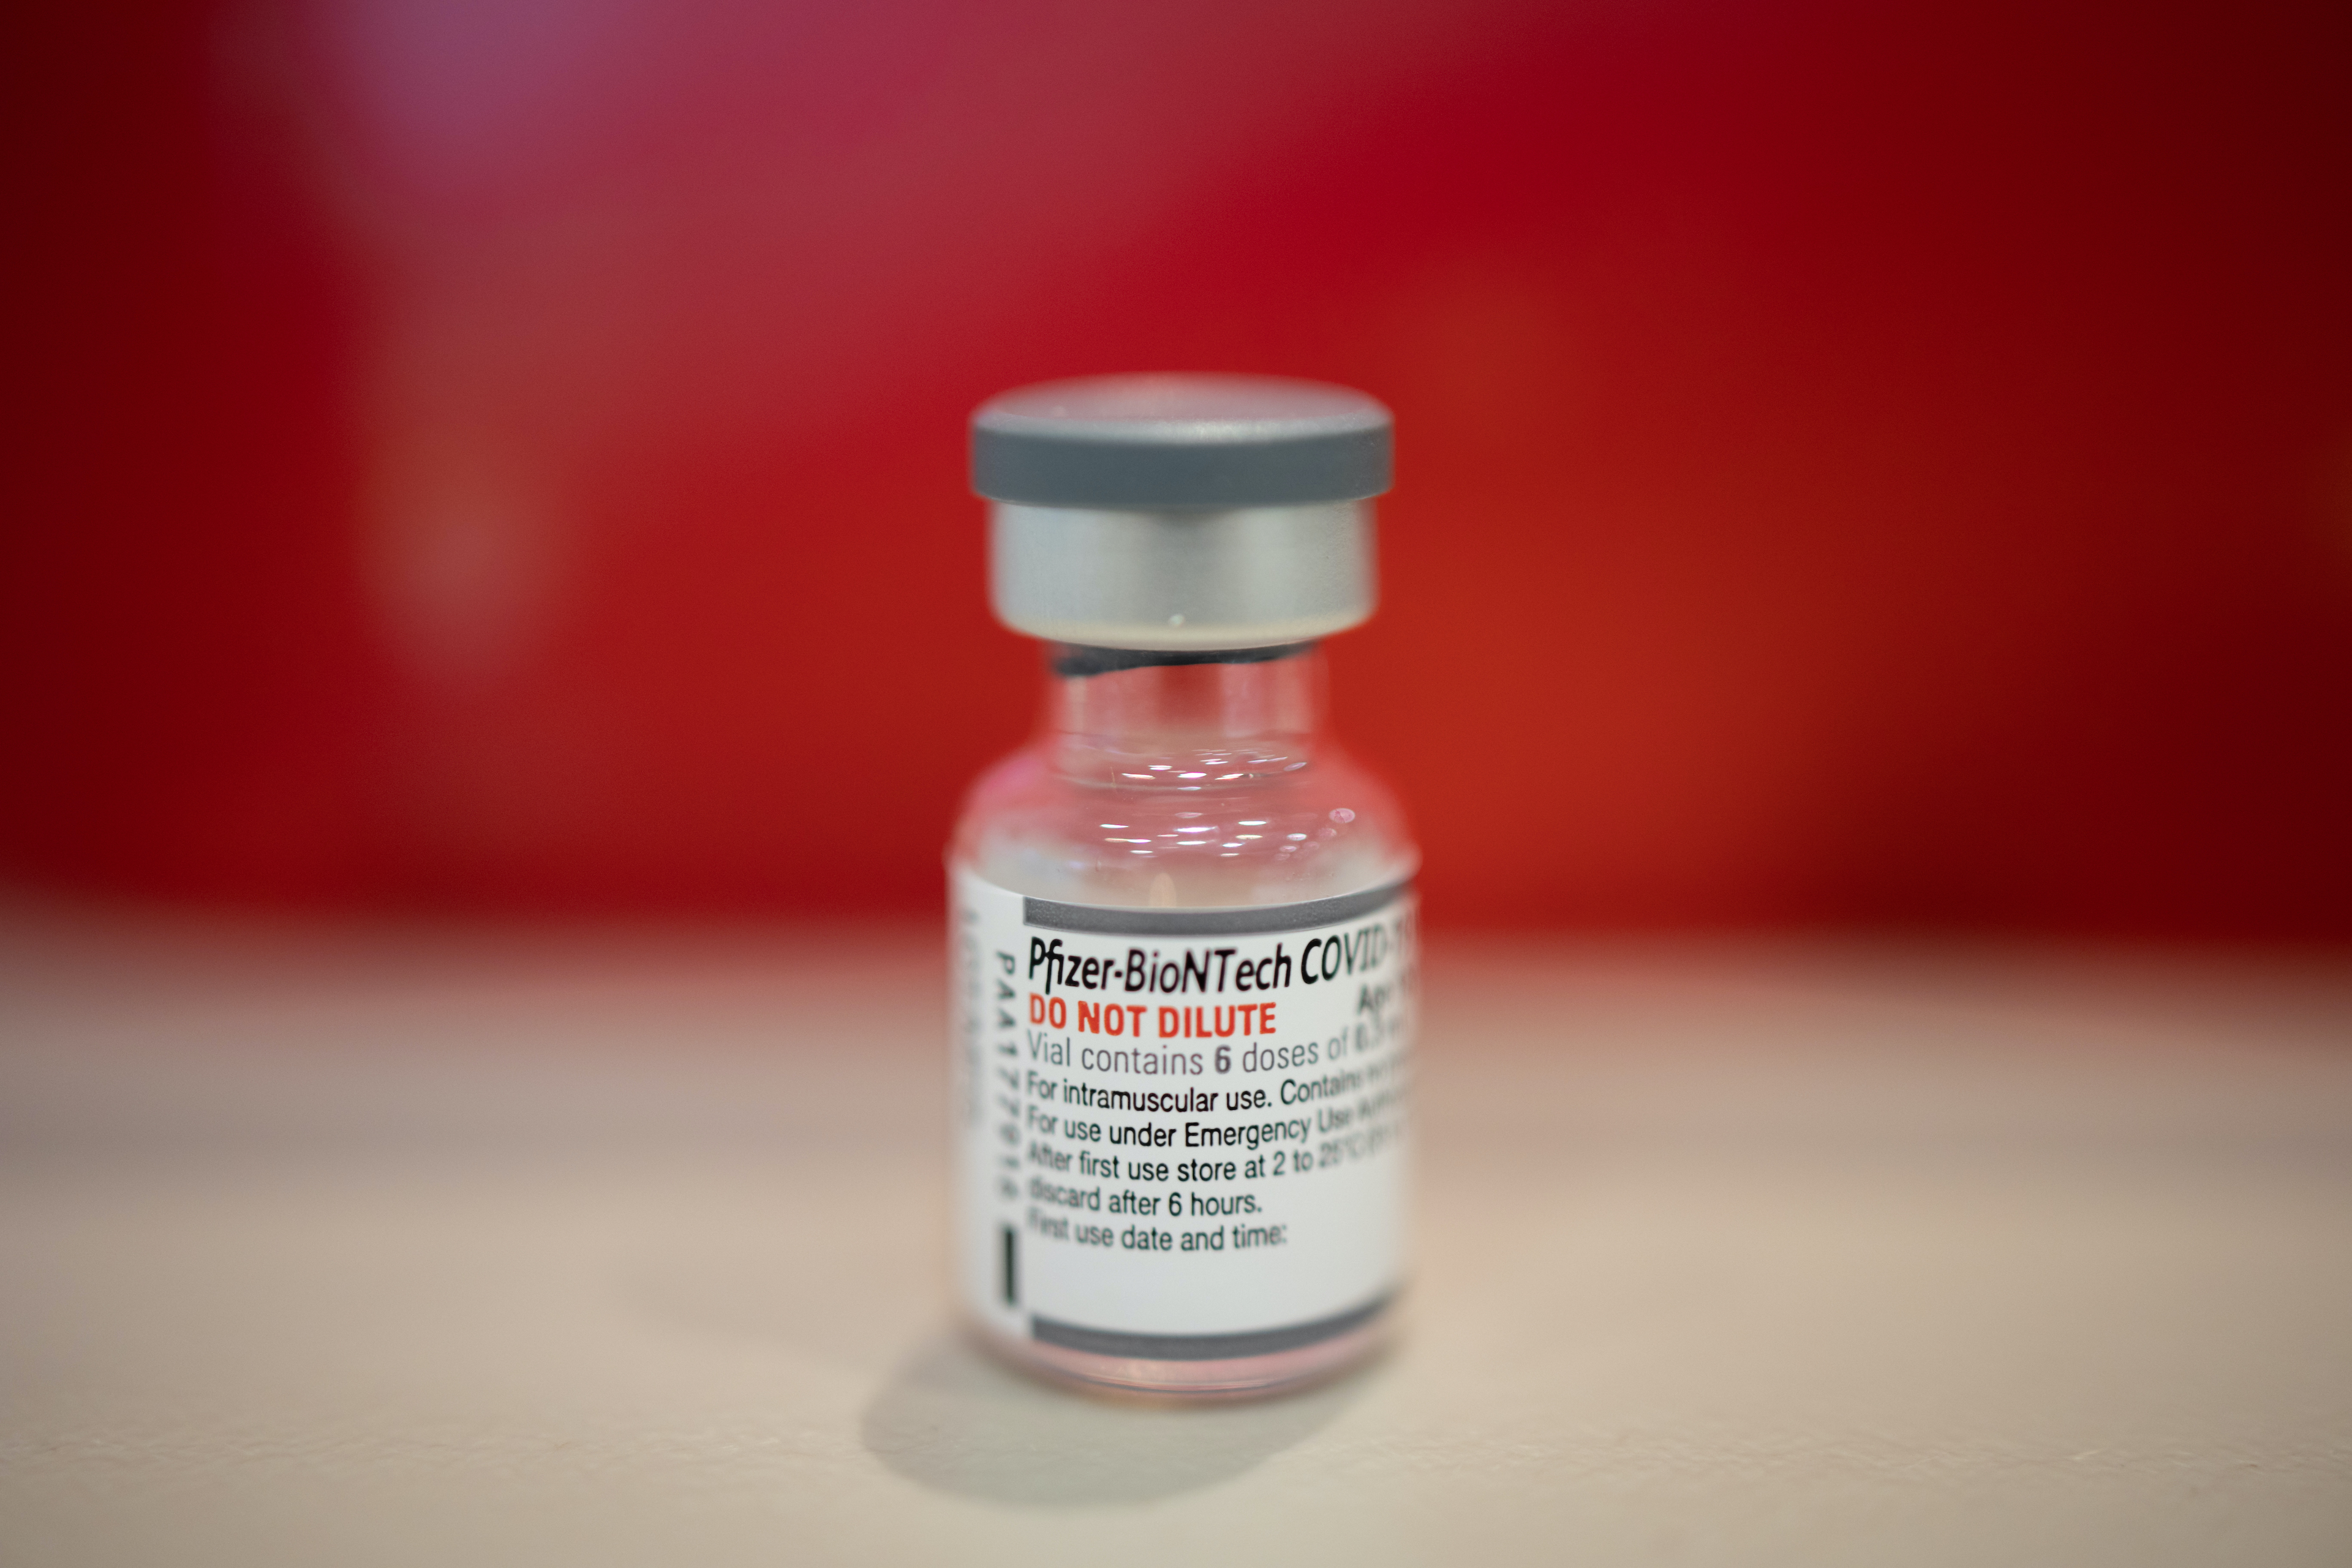

How Pfizer Won the Pandemic, Reaping Outsize Profit and Influence

The grinding two-plus years of the pandemic have yielded outsize benefits for one company — Pfizer — making it both…

Read More » - Health